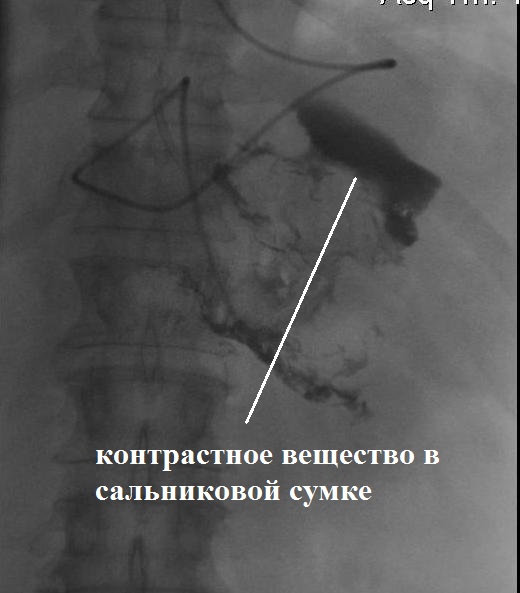

При выполнении рентгеноконтрастного исследования выявлено сообщение сальниковой сумки с полостью абсцесса брыжейки тонкой кишки (рис. 11).

Рис. 11. Контрольное рентгеноконтрастное исследование на 56-е сут болезни. А — рентгенофистулография; Б — схема сообщения полостей

В дальнейшем проводились этапные эндоскопические секвестрэктомии на фоне активного промывания полостей абсцесса брыжейки тонкой кишки и сальниковой сумки раствором хлоргекседина через дренажные трубки (рис. 12).